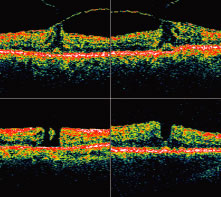

holes. Ophthalmology 1995;102:748 24. Puliafito CA, Hee MR, Lin CP et al. Imaging of macular diseases with optical